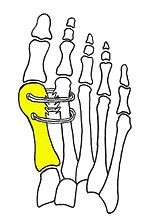

Syndesmosis procedure addresses specifically the two fundamental problems of metatarsus primus varus deformity that gives rise to the bunion deformity. They are leaning and instability of the first metatarsal bone . Syndesmosis procedure uprights the leaning first metatarsal bone with strong binding sutures between it and the second metatarsal bone (Fig. 2) and then also stabilizes it uniquely by creating a fibrous connecting bridge between these two bones (Fig. 3,4). First metatarsal bone can be readily realigned is because by definition of the metatarsus primus varus deformity its first metatarsal is abnormally loose and mobile.